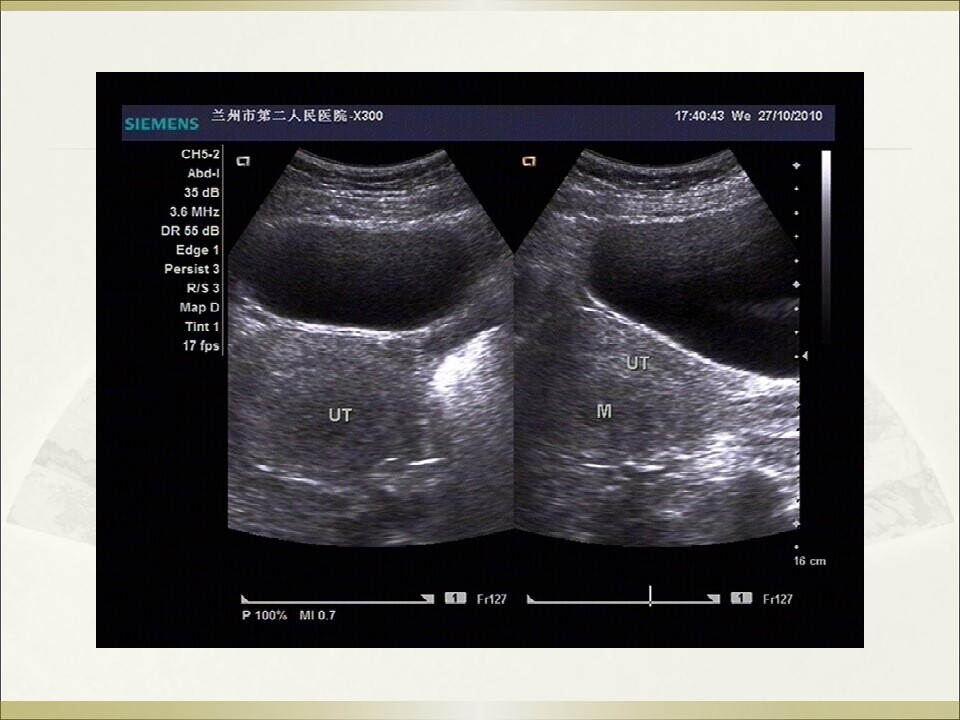

妇产科急腹症是指因妇科疾病引起的剧烈的急性腹痛,可以是原有疼痛突然加剧,或原无疼痛突然发生,是病因较多的常见病,特点是发病急、病变进展快、病情重,需要及时作出病因诊断及治疗。